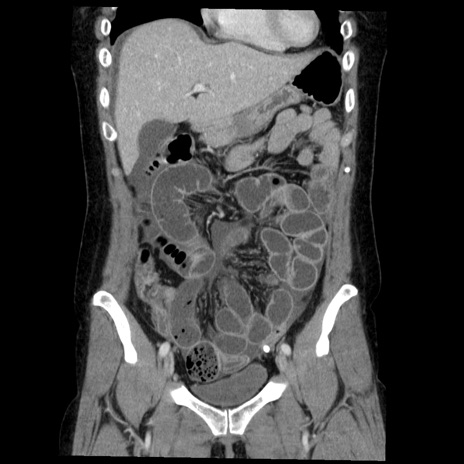

症例6(冠状断像)

【症例】50歳代女性

【主訴】下腹部痛

【現病歴】本日朝より下痢2回あり。 昼食を食べた後、嘔吐3回、下腹部痛認め、症状軽快せず、当院救急搬送。

最終食事:本日昼(生ものなし)。 昨日の夜、刺身を食ぺたとのこと。周囲に同様の症状の者なし。普段、排便は毎日あるとのこと。

【既往歴】卵巣癌術後(8年前に当院で卵巣摘出)

【身体所見】 意識清明、腹部:平坦、腸蠕動音→、やや硬、下腹部自発痛・圧痛あり、反跳痛あり、筋性防御なし。

【データ】WBC 16000、CRP 0.01